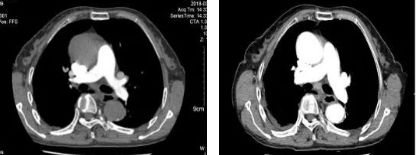

两个月后赵老太如约来门诊复查,胸部增强CT显示肺动脉血栓已经明显溶解吸收,肿瘤缩小,但后纵隔淋巴结出现增大,隆突下见4*5cm不均匀等低密度液性暗区。

胸部增强CT纵膈窗

后纵膈弧片状液性密度影、纵膈淋巴结肿大